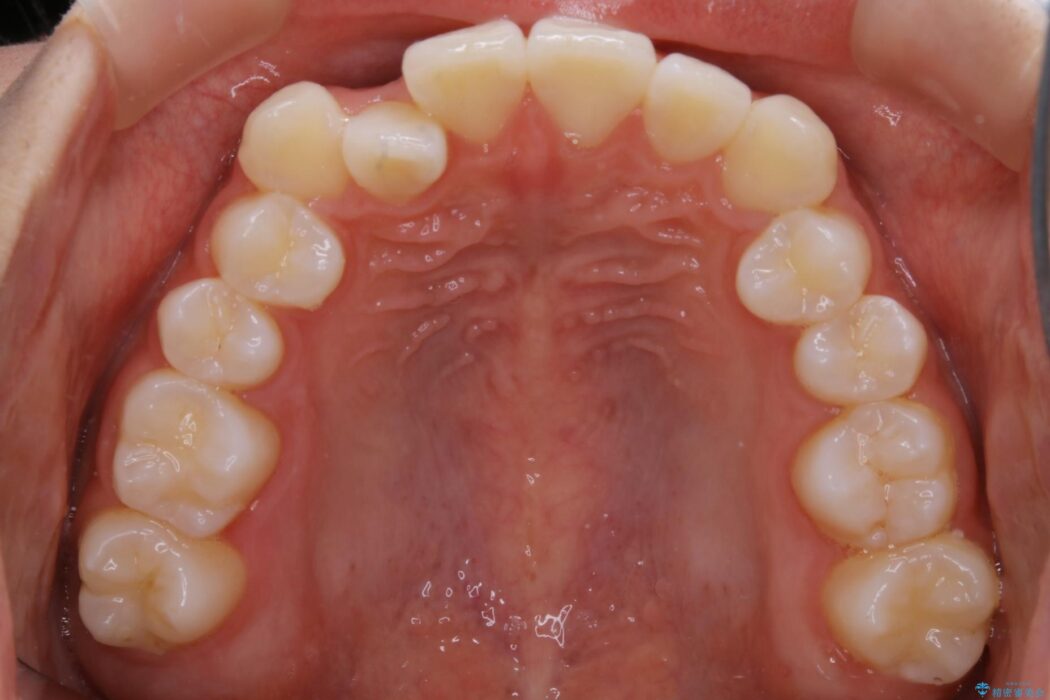

治療後について

正常な噛み合わせ位置へと改善したことにより奥歯で噛みしめることができ、加えて見た目も受け口から変わって大変ご満足いただけました。